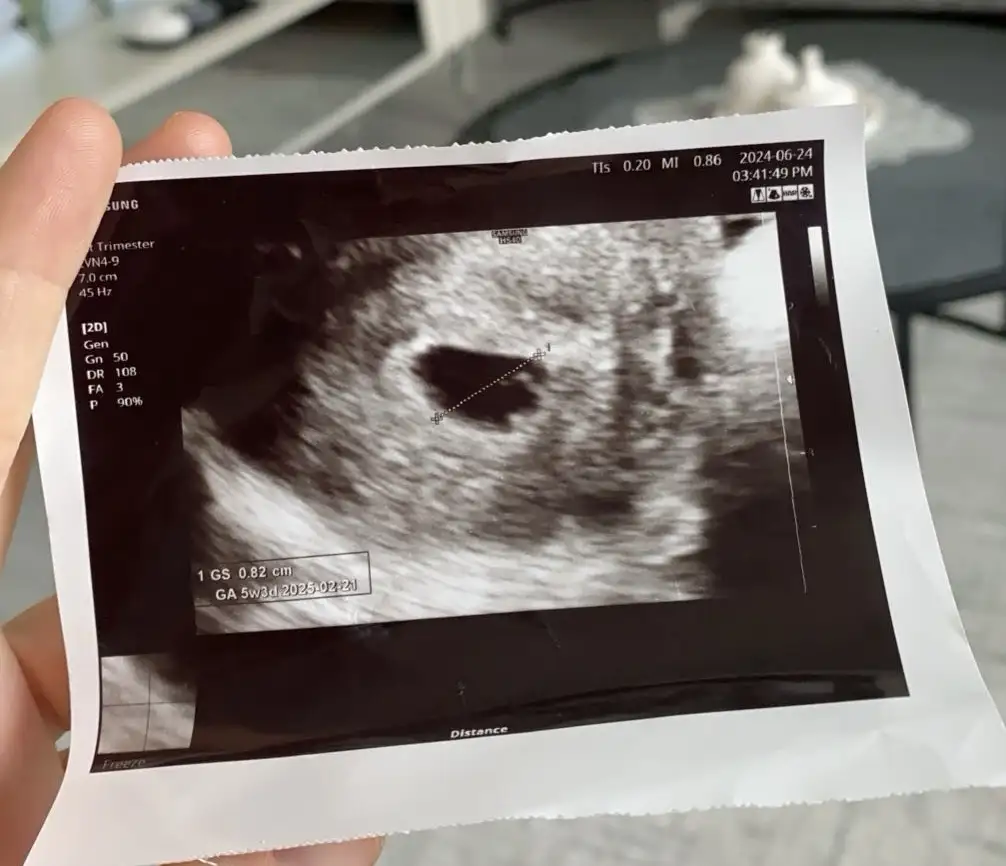

Yaaa ne güzel ayniyiz senin kese nasıl sende atabilirsen bakalımAynıyız canım bende 5+4 üm bugün gördük keseyi

Senin GA GS değerlerin kaç ultrasondaYaaa ne güzel ayniyiz senin kese nasıl sende atabilirsen bakalım

Masaaallah Allah sağlıkla kucağına Almayı nasip etsin ya benim doktor hiç birsey söylemedi hiç hiç memnun kalmadım yani değiştireceğim doktorumu hemen hemen benziyor keselerSenin GA GS değerlerin kaç ultrasonda![]()

Kese boş değil ki haftaya kalp atışını duyarsın.Kızlar merhaba Nasipse bende subat Ayı Annesi olacağım 5+4 deyim bugün kontrol için gittim kese gözüktü ama doktor yolk kesesi ile ilgili birsey söylemedi şimdide bos gebelikte ilgili şeyler okuyunca biraz endişe ettim sizce varmı yolk kesesi anlayan varsa çok sevinirim.